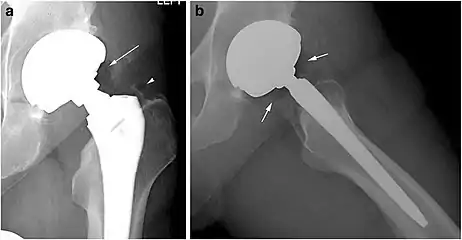

X-ray of a hip with hip replacement and pneumarthrosis, in this case aseptic.